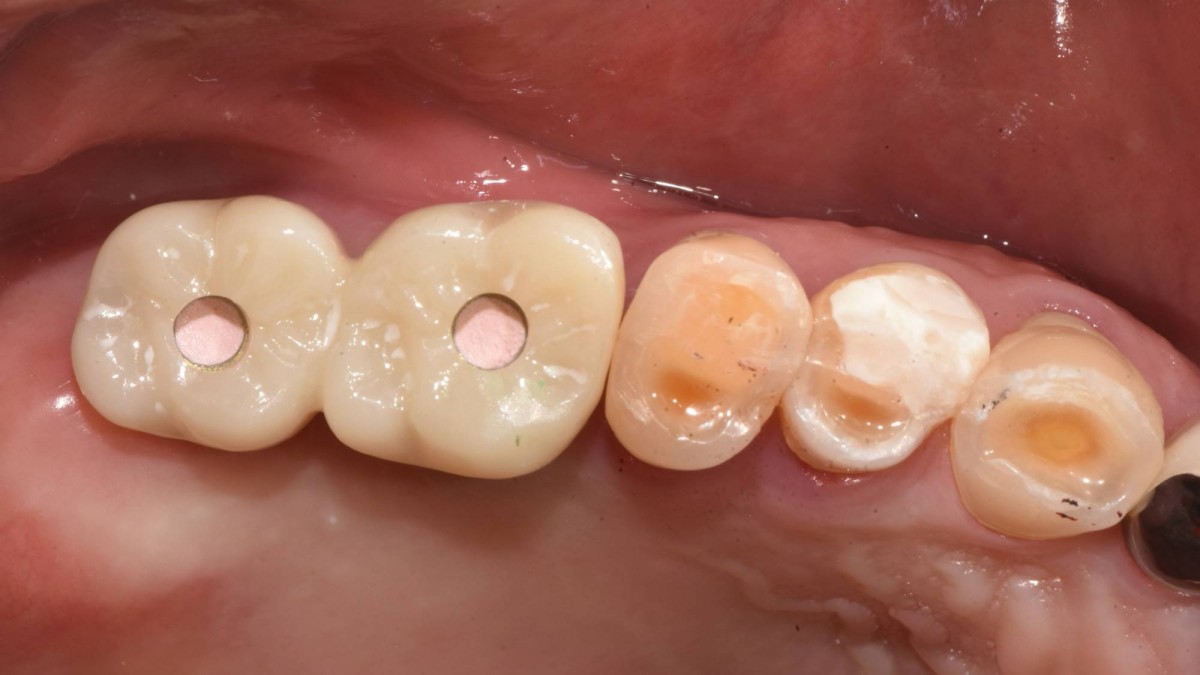

Socket Lift and Implant Placement in the right maxilla.

<GCacg> A 56-year-old male patient complained of pain in the right upper and lower jaws. And he wanted the upper first molar to be pulled out first.